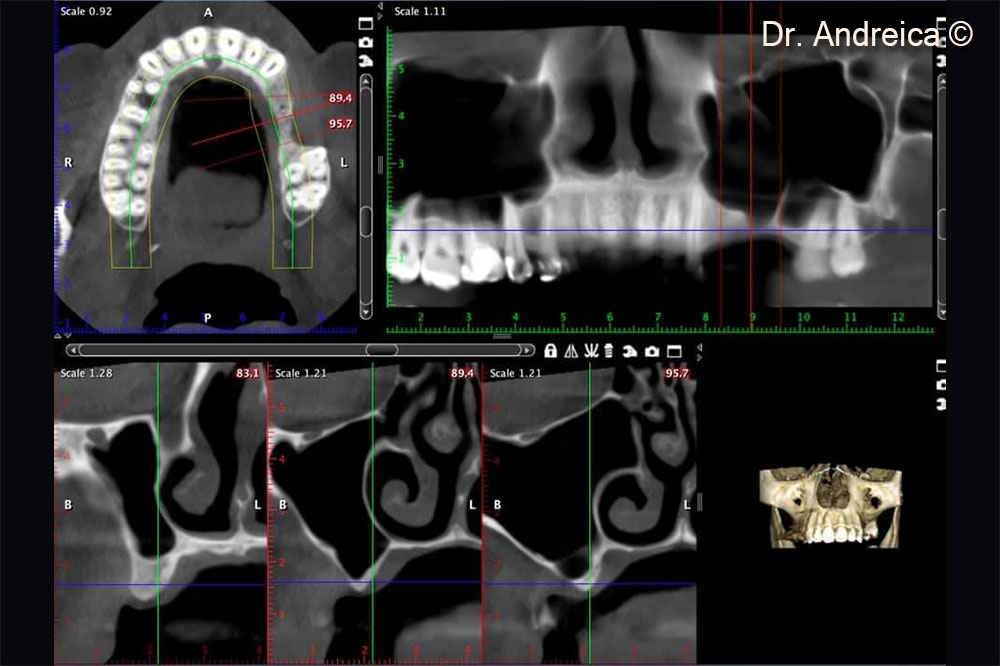

CBCT scan shows a very thin crest vertically and horizontally especially in the molar region and  the presence of a transversal septa. The osteo-meatal complex is patent